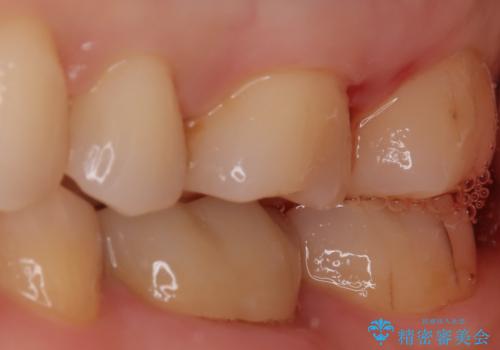

【セラミックインレー】適合の良いセラミックインレーを入れたい。

- 毎回フロスが引っかかることを気にされており、改善のため適合の良いセラミックインレーで修復しました。

以前に他院で詰め物をいれた時は、フロスが毎回ちぎれて大変だったそうですが改善して喜んでおられました。

当院のセラミックインレーは必ずラバーダムを使用して接着しています。